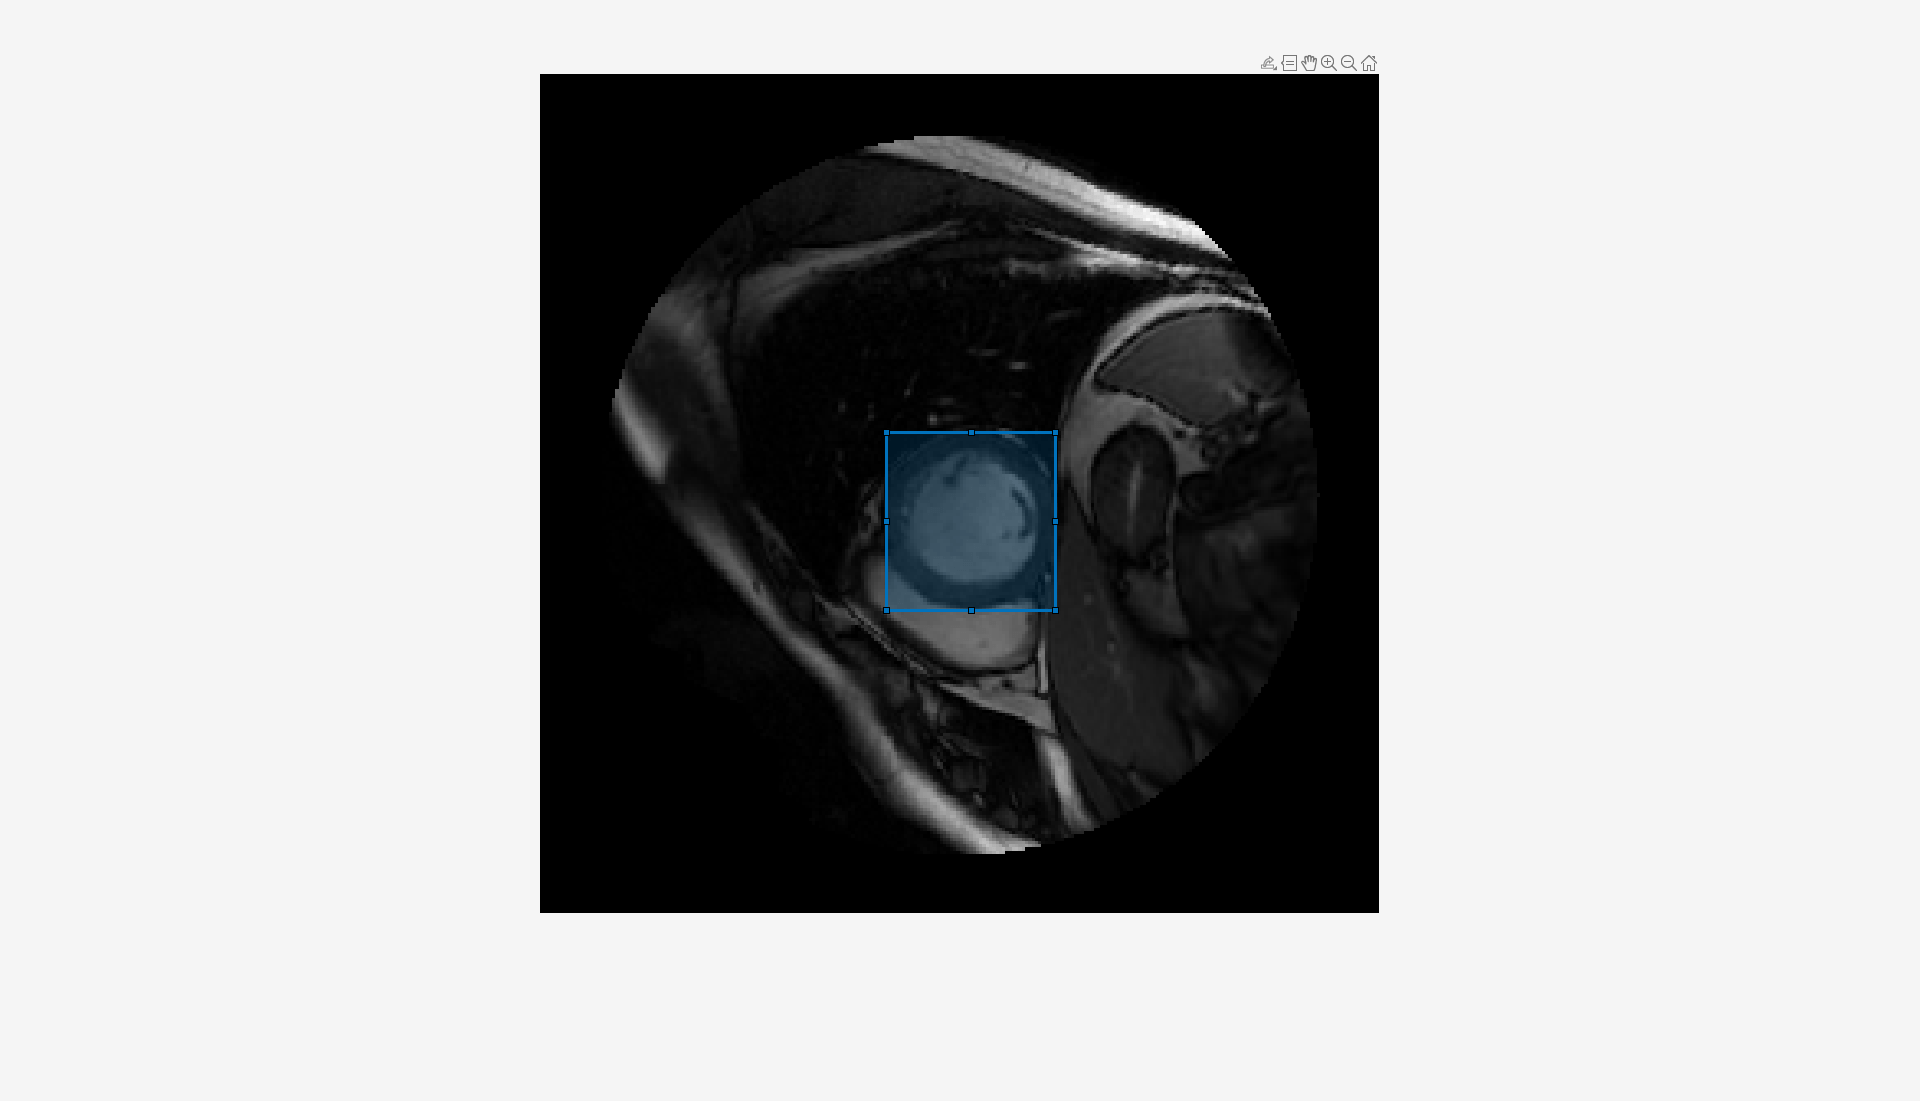

Draw an ROI that contains an object to segment as a Rectangle object on the image by using the drawrectangle function.

roi = drawrectangle(ax);

To segment the object, run the MedSAM decoder on the image embeddings using the segmentObjectsFromEmbeddings object function. Specify the bounding box visual prompt BoundingBox as the position of the rectangle ROI.

mask = segmentObjectsFromEmbeddings(medsam,embeddings,size(img),BoundingBox=roi.Position); overlayedImg = insertObjectMask(rescale(img),mask);

Visualize the segmentation mask overlaid on the image in the image display.

dispIm.CData = overlayedImg;

Analyze the segmented object using the analyzeObject helper function provided at the end of this example. The analyzeObject helper function performs radiomics analysis in the region indicated by the segmentation mask returned by the MedSAM decoder, and extracts key features such as surface area, major axis length, minor axis length, mean intensity, and intensity variance of the segmented region. The function then displays these key radiomics features as text near the segmented region in the image.

analyzeObject(img,mask,t,roi.Position);